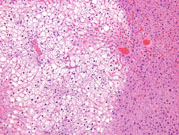

Periportal fatty change. The large, sharply delineated, clear vacuoles represent fat that has been dissolved during tissue processing. Deposition of fat in the hepatocyte cytoplasm often displaces the hepatocyte nucleus to the periphery of the cell.